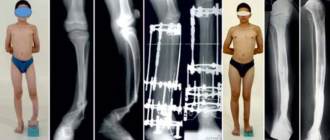

Ложный сустав: причины заболевания, основные симптомы, лечение и профилактика Псевдоартроз представляет собой патологическое состояние,